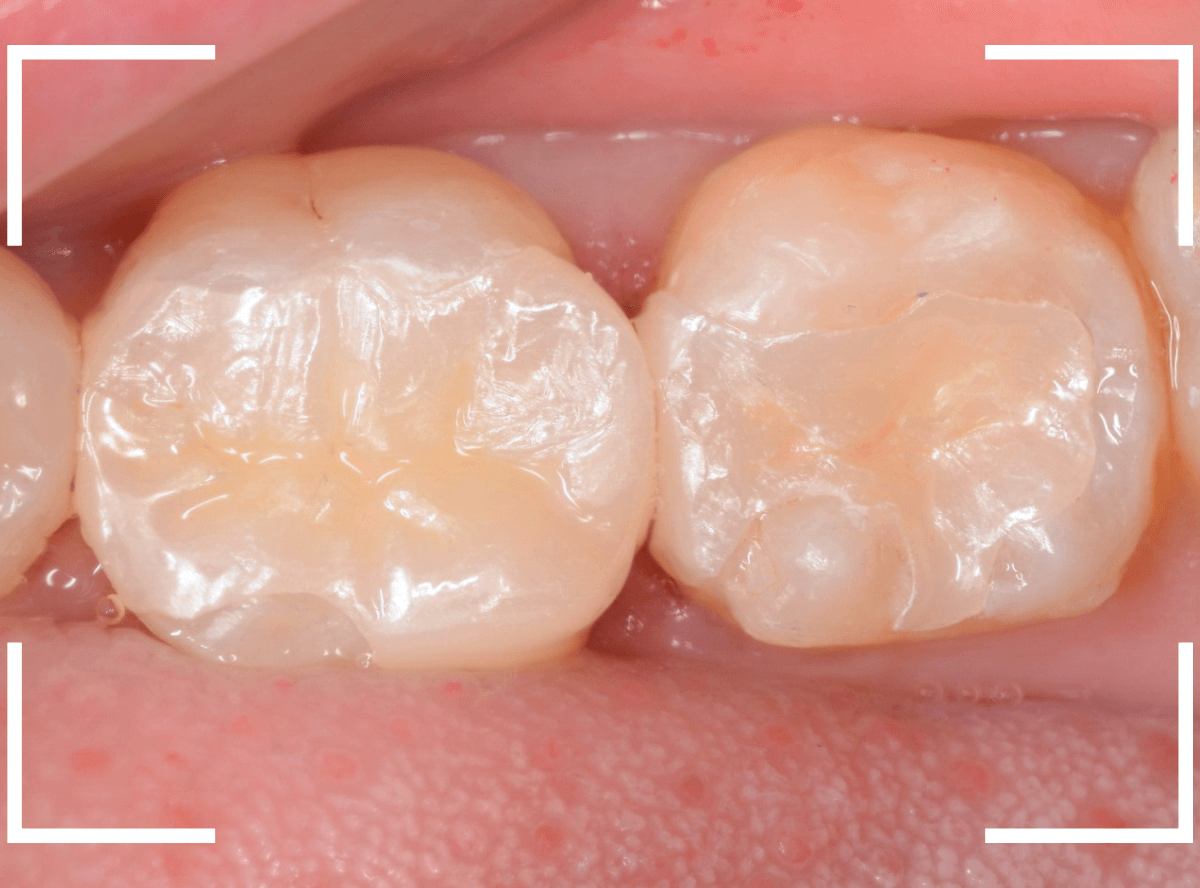

set後の写真です。

患者さんにも満足していただける仕上がりになりました。

治療前後の比較写真になります。